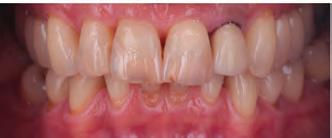

Esthetic patterns demanded by society have stimulated patients to search for dentofacial harmony and improve their appearance. Dentistry allows patients to obtain their desired goals and provides them with great smiles.1,2 One of the most popular materials in dentistry is composite resin. These are used due to their relatively low cost, availability, and bonding efficiency.3,4 They also offer good predictability, acceptable longevity, and less invasive restoration techniques, and they cost less than indirect restorations.5 Thus, when restoring anterior teeth, it is up to the clinician to take advantage of the full potential of direct restorations to provide anatomy, function and esthetic results.5,6

To achieve the full potential of direct restorations, knowledge of the optical properties of dental tissues and restorative materials in terms of individual characteristics such as chromaticity, opacity/translucency, and restorative techniques is necessary. Appropriate contouring and polishing methods are also primordial to achieve restorations that blend into the tooth structure and defy detection.6,7 Restoring a tooth to its ideal shape, function, and esthetics with composite resins requires excellent attention to detail and technical proficiency.8 Due to the rapid advancements in adhesive technology, incorporating composites into tooth structure with minimal or no cavity preparation has become feasible, allowing for a minimally invasive or non-invasive approach.9

Techniques

Free-hand: This technique involves the addition of composite layers without the use of any matrix or containing system.23 It relies on the dentist’s ability to manipulate the material in a cavity preparation or to address various issues, such as replacing missing dental tissue in an incisal edge, repairing enamel defects, closing diastemas, or filling small cavity preparations.13,16 Practitioners may choose between different viscosities of resin composite, some opting for flowable or less viscous materials and some preferring higher viscosity, such as conventional composites.5,13 Instrumentation varies from using just the tip of the flowable material to injecting and smoothing thin-bladed instruments and brushes for conventional materials.3 (Fig. 2)

For most free-hand techniques, a conventional mylar strip is necessary.3,24 These strips aid in composite placement and the common “pull-through” technique,3,25 which involves pulling material through the interproximal with the mylar strip to fill proximal areas. While effective in skilled hands, this technique can be challenging and impractical for novices.24 Furthermore, it only works when utilizing very “waxy,” nonsticky, firm materials and is contraindicated for flowable and sticky materials.26